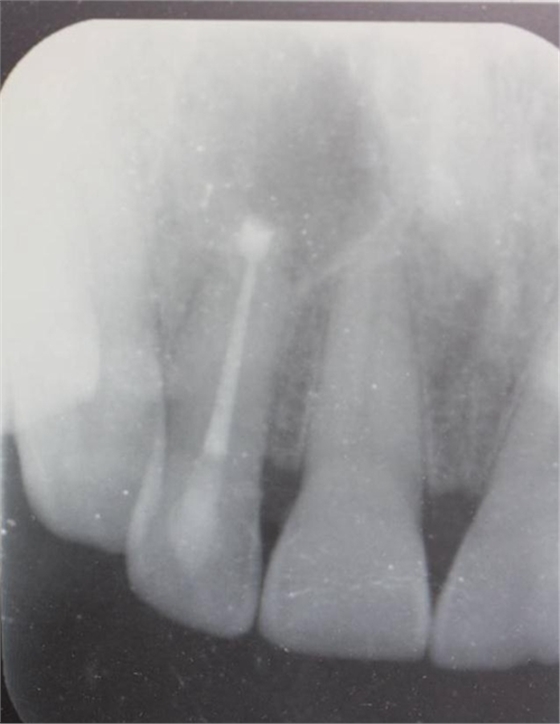

圖1.患者在根管術(shù)前的根尖片影像檢查:12有開(kāi)髓孔,根尖有橢圓形陰影。

圖22.術(shù)后的x根尖片影像情況。12根尖區(qū)MTA充填完好。